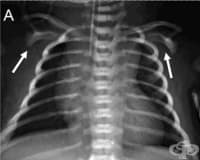

Хроничната тромбемболична пулмонална хипертония (ХТПХ) е следствие на поредица от емболии, водещи до...